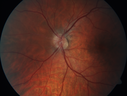

31 year old man with vision loss in the right eye more than the left eye. He has an anaplastic astrocytoma diagnosed 10/2017 the first one was 10/2014. These are different locations. They are treating them with Chemotherapy and Avastin. It might be that one might have spread from the other. He was clean for 3 years. He is on Avastin and Temozolomide but his blood counts have been good. December 2017 he had a herpes superficial infection in the right eye which responded to treatment. The last neurosurgery was October 2017. Going to Duke June 5 and seeing a neuroophthalmologist there. VA OD: Dcc20/40 PH20/25 NccJ5 VA OS: Dcc20/16 PH20/10 NccJ1+ His fundus is presumably nocardia, pneumocystis, aspergillis or cryptococcus. His LP was negative and he was tried on a course of antifungals. He was then lost to followup

Multifocal Choroiditis - Pneumocystis - aspergillis - cryptococcus632 views31 year old male with anaplastic astrocytoma on chemotherapy with mild vision loss in the right eye. LP did not reveal organism. He was placed on a trial of anti-fungal medications and lost to follow-up00000